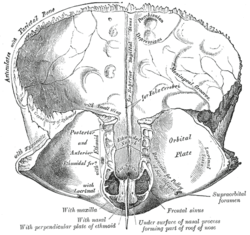

Left parietal bone. Inner surface.

Frontal bone. Inner surface.